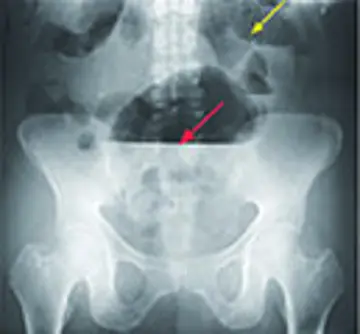

طب داخلی - صفحه 14